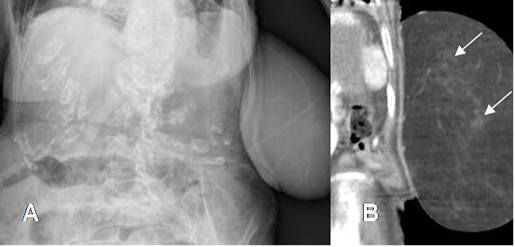

Fig 164. Fibrolipoma.

A: Rx de abdomen. Gran prominencia en la pared abdominal izquierda.

B: TAC reconstrucción coronal. Masa con densidad de grasa, por lipoma. Presenta algunas zonas densas, por contenido fibroso.